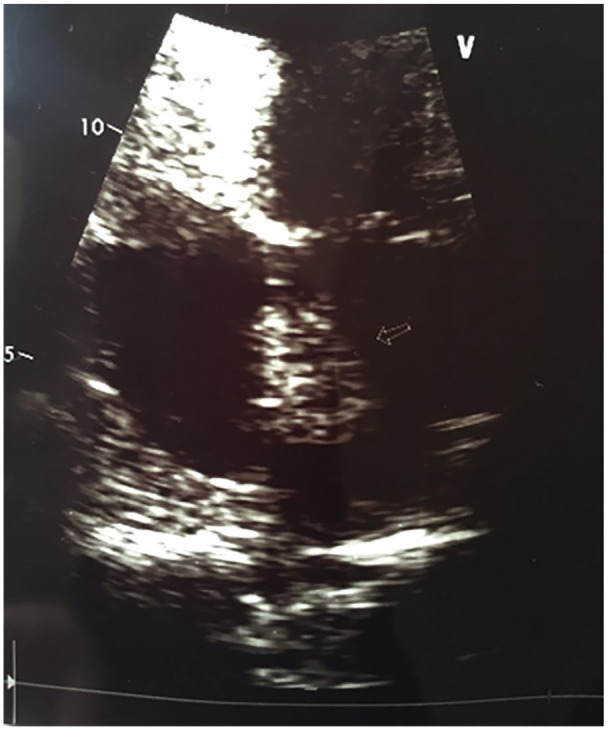

卡尼综合征(CNC)是一种罕见的综合征,其特征是皮肤色素斑和多种肿瘤,尤其是心肌瘤、分裂瘤和内分泌肿瘤。该病通常为常染色体显性遗传,大多数病例都存在 PRKAR1A 基因突变。男性不育是 CNC 表型的一部分,主要与大细胞钙化性 Sertoli 细胞瘤(LCCSCT)有关。我们描述了一例 30 岁的男性卡尼综合征患者,该患者表现为严重少精症和原发性色素结节性肾上腺皮质疾病(PPNAD)。在随访过程中,严重少精症和精液运动能力受损的情况持续存在,患者还被诊断出患有复发性心脏肌瘤和 LCCSCT。分子检测发现了一种新型 PRKAR1A 突变,涉及外显子 4 至 7 的缺失。我们的研究结果表明,无论是否存在睾丸肿瘤,该突变都会导致 PRKAR1A 单倍体缺乏,这可能与男性不育直接相关。因此,在患有 CNC 的男性患者中,PRKAR1A 基因突变的检测可作为不育症的预测指标。本病例报告说明了早期考虑和处理 CNC 男性患者不育症的重要性。

Carney Complex (CNC) is a rare syndrome characterized by spotty skin pigmentation and multiple neoplasms, notably cardiac myxomas, schwannomas, and endocrine tumours. It is often inherited in an autosomal dominant manner with PRKAR1A gene mutations found in the majority of cases. Male infertility is established as part of the CNC phenotype and is largely associated with Large cell calcifying Sertoli cell tumours (LCCSCT). We describe a case of a 30-year-old male patient with Carney Complex, presenting with severe oligoasthenozoospermia and primary pigmented nodular adrenocortical disease (PPNAD). During follow-up consults, the severe oligozoospermia and impaired semen motility persisted and the patient was also diagnosed with a recurring cardiac myxoma and LCCSCT. Molecular testing identified a novel PRKAR1A mutation involving a deletion of exons 4 to 7. Our findings suggest this mutation causes PRKAR1A haploinsufficiency, which may be directly linked to male infertility, irrespective of the presence of testicular tumours. Accordingly, in male patients with CNC, detection of a PRKAR1A gene mutation may serve as a predictive marker for infertility. This case report illustrates the importance of early consideration and management of infertility in male patients diagnosed with CNC.